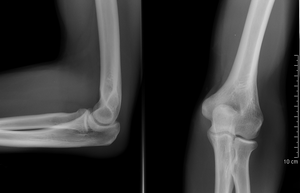

التصوير الشعاعي إنگليزية: Radiography: وهو يستخدم الأشعة السينية لرؤية الأجزاء غير المرئية أو صعبة التصوير. الهدف الأساسي من الأشعة السينية المستخدمة في التشخيص هو تصوير داخل الجسم، وبشكل خاص العظام والتي يمكن رؤيتها بدقة مثلى (128 تدرج للون الرمادي).

Projectional radiography